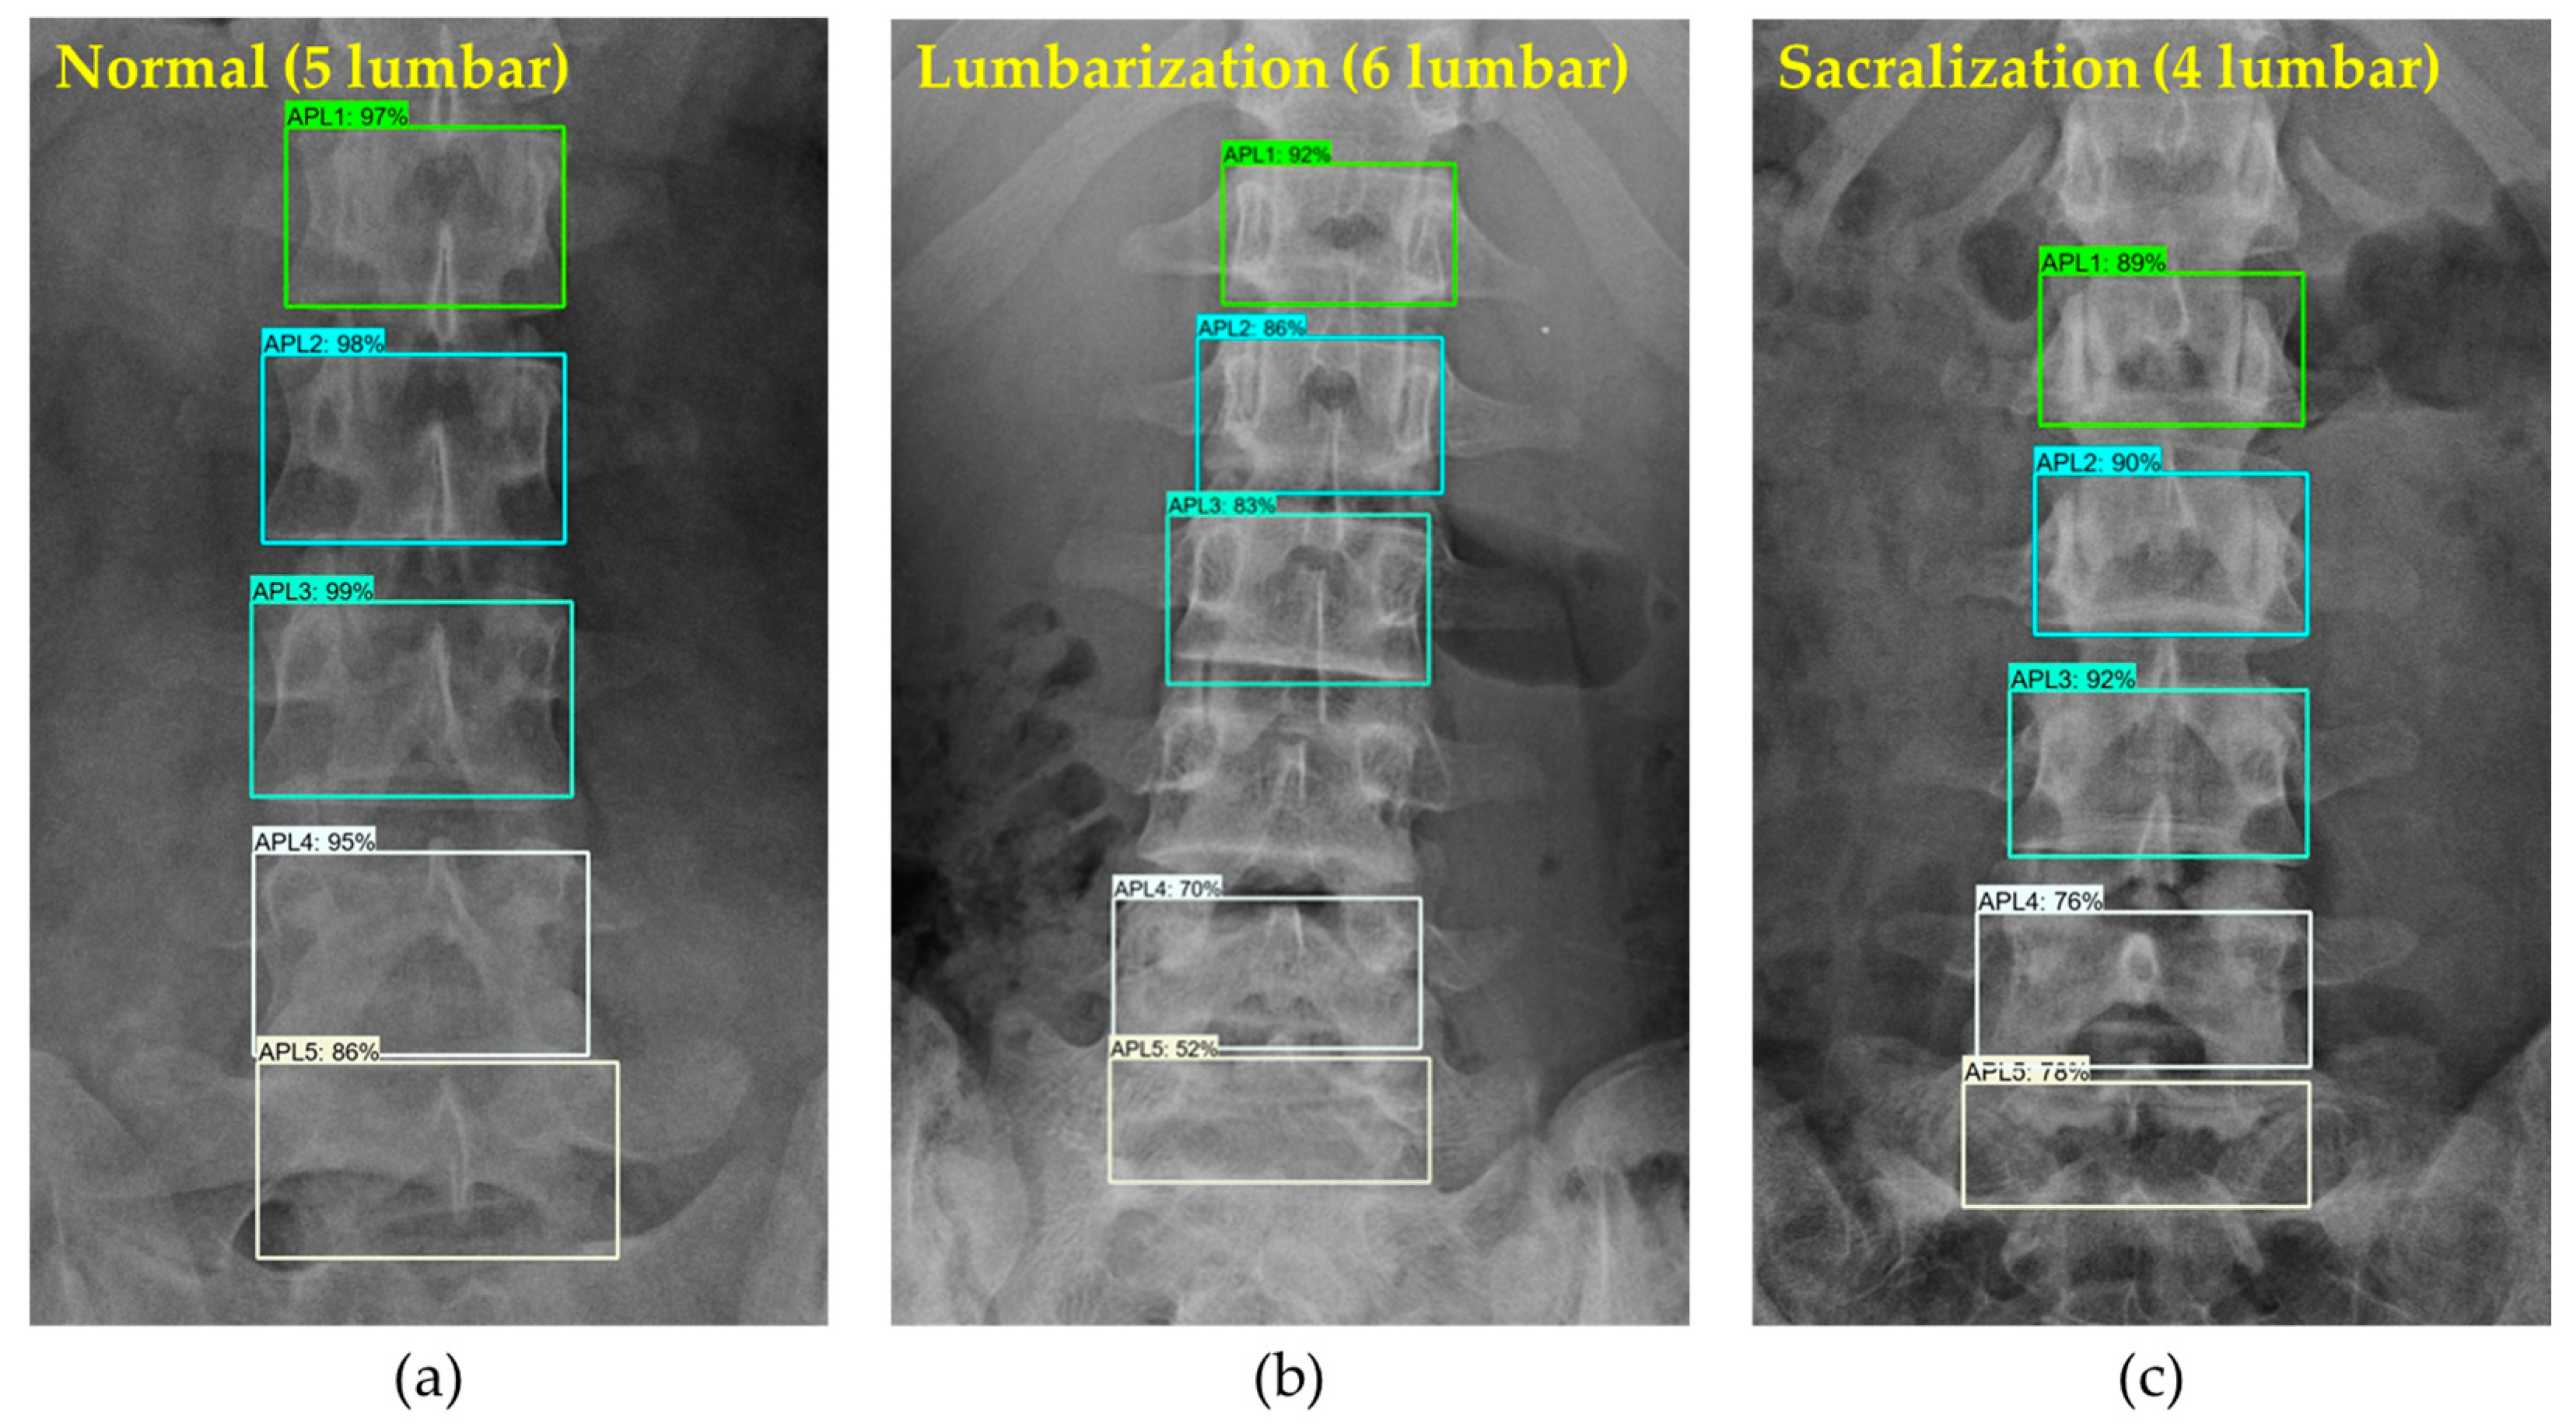

2.2.3. LSTV

3.1. Lumbar Vertebrae Detection